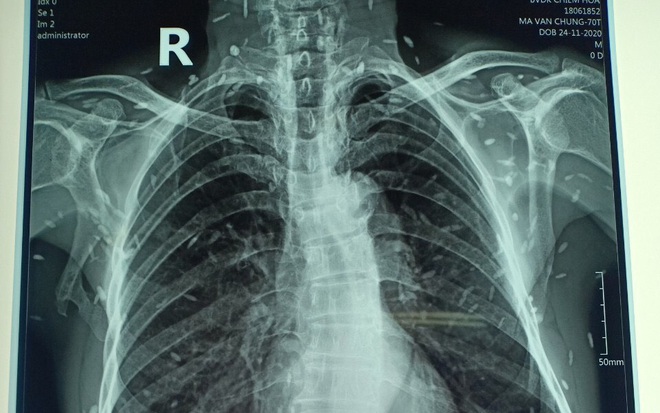

• Chụp X-quang ngực để kiểm tra hình ảnh phổi.

Đối với những ai có triệu chứng như ho ra máu, đau ngực hoặc khó thở kéo dài, việc đến gặp bác sĩ để được tiến hành các xét nghiệm như xét nghiệm đờm, chụp X-quang ngực và xét nghiệm máu là rất cần thiết để chẩn đoán bệnh.